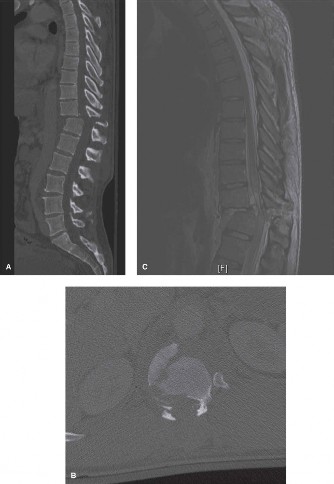

The correct answer is (C). While x-rays and a CT scan may be helpful in evaluating overall alignment of the cervical spine as well as possible bony changes, an MRI would be the best imaging modality to visualize any neurologic involvement leading to the patient’s deficit. With the patient’s history, an infectious etiology is highly likely. While a bone scan can demonstrate increased activity in an area of infection, it does not help localize the exact location and extension of neurological involvement. In the event that an MRI is contraindicated, a CT scan, ideally with

intrathecal contrast, would be a reasonable alternative. Advanced imaging is shown inFigure 1–10. What is the most likely diagnosis? 1. Ossification of the posterior longitudinal ligament

Figure 1–10

Discussion

The correct answer is (B). The T1 sagittal MRI demonstrates an epidural process that extends behind the C2, C3, and C4 vertebral bodies. There is destruction of the C3–4 disc space, which likely represents discitis/osteomyelitis. The epidural mass is most likely an abscess originating from the C3–4 disc space. OPLL, or ossification of the posterior longitudinal ligament, would typically be seen as an intermediate

signal along the posterior aspect of the disc space/vertebral bodies and would not be associated with disc space destruction. Metastatic tumors and primary bone tumors more commonly involve the vertebral bodies themselves and do not typically cause increased signal within the disc space itself. Extruded disc herniations can extend behind the vertebral bodies but are not as large as depicted in these images and do not lead to signal changes within the disc space with bony involvement.